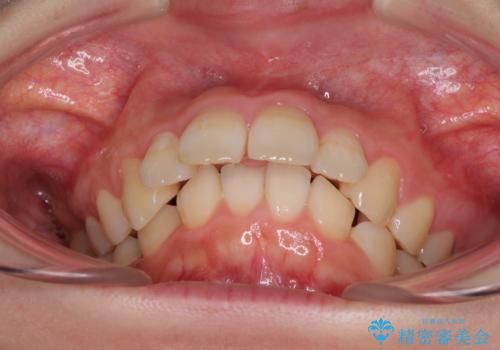

下顎は左右2番目の歯が2本欠損しており、上下前歯の前後的な位置は著しくずれている状態でした。

骨格的にも上顎骨が前突傾向にあり、極端な過蓋咬合になっていました。

強い咬合力に抵抗するように歯を動かす必要があるにもかかわらず、上顎第一大臼歯が1本欠損しているため、治療は困難を極めることが予想されました。